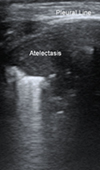

Echo-Guided Recruitment of Lung Atelectasis after Pediatric Cardiac Surgery

Lung ultrasound is a useful tool in intensive care unit. In addition to imaging various lung and pleural diseases, LUS could guide interventional proc... Read more

10.36959/582/410